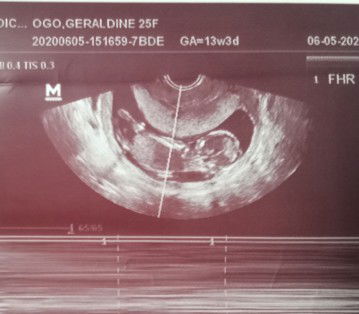

Me......27 weeks n tummy q....ksad ksi d dw nia q mhal...at mhal nia un gf nia n 13 yrs n dw ksi cla.ngkabalikan dw cla ng may.nbubtis nia q july...npka immature nia s age nia 40 sv msya dw cia bsta alm nia mgkka ank cia prang pinatunyan lng nia pgklalake nia..msya dw cia ok cla ng gf nia khit dw nkbuntis cia.sv ng girl khit dw nbuntis q d nia ppaubya un lalake...sna mging msya cla..c god n bhala knila..dgital mn karma